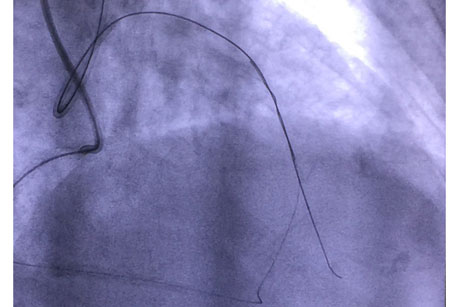

手术在11月6日进行,由赵慧强主任、张文广副主任医师担任术者。手术穿刺了两侧的桡动脉,均置入指引导管,微导管支持下送入前向导丝拟开通CTO病变,但闭塞病变处严重钙化,经尝试不能通过闭塞段到达远端真腔。鉴于右冠向左前降支发出良好的侧枝循环,此时果断地采用逆向导丝技术,首先干预右冠近端及远端病变,搬开逆向导丝应用的“绊脚石”,在微导管支持下专用导丝依次通过右冠后降支→侧枝循环→间隔支→前降支闭塞病变远端,逆行进入前降支闭塞病变远端,但逆向微导管未能送入侧枝内,遂改变策略再反复调整前向导丝前进,最终前向导丝与逆向导丝“抱紧”,成功通过闭塞病变到达前降支远端病变真腔,顺利完成支架置入。术后患者未再发作胸憋、胸痛,已顺利出院。